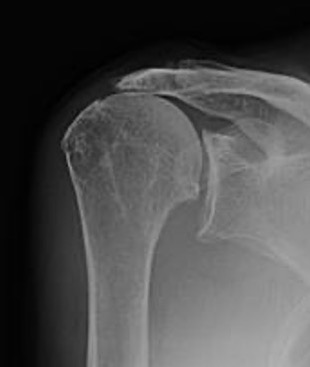

Rotator cuff arthropathy

Anatomic shoulder arthroplasty in cuff deficient shoulders

High failure rate

- superior migration / edge loading

- rocking horse phenomenon